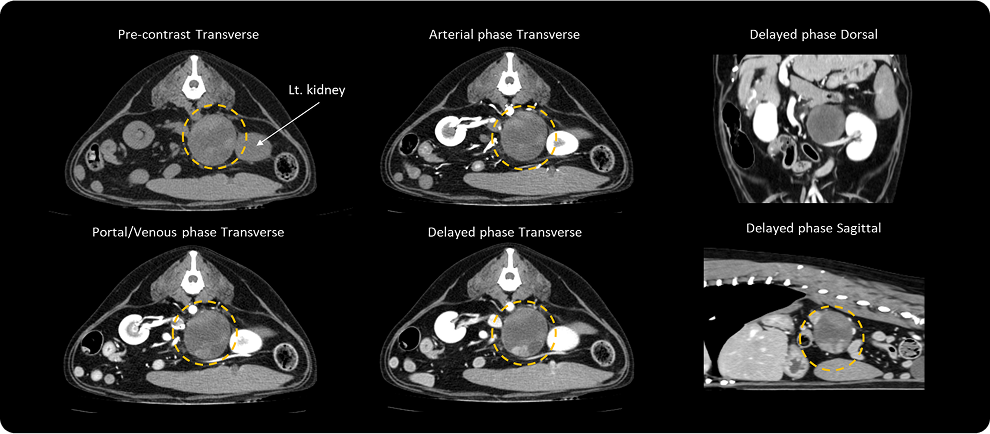

· CT 검사

초음파 검사 결과에서 종양성 병변의 가능성이 높을 경우,

수술적인 치료 방법을 선택하기 위해 CT 촬영을 진행할 수 있습니다.